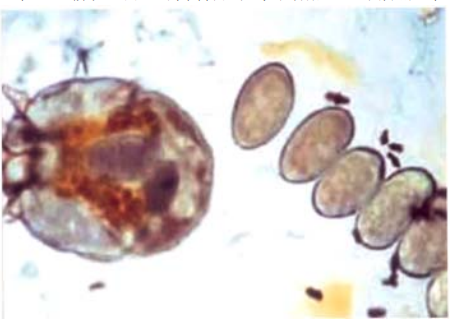

40 一位 70 歲老翁主訴會陰部奇癢無比,顯微鏡下檢查發現如下圖,這是何種感染?

(A)陰蝨 (B)體蝨 (C)疥瘡 (D)塵蟎